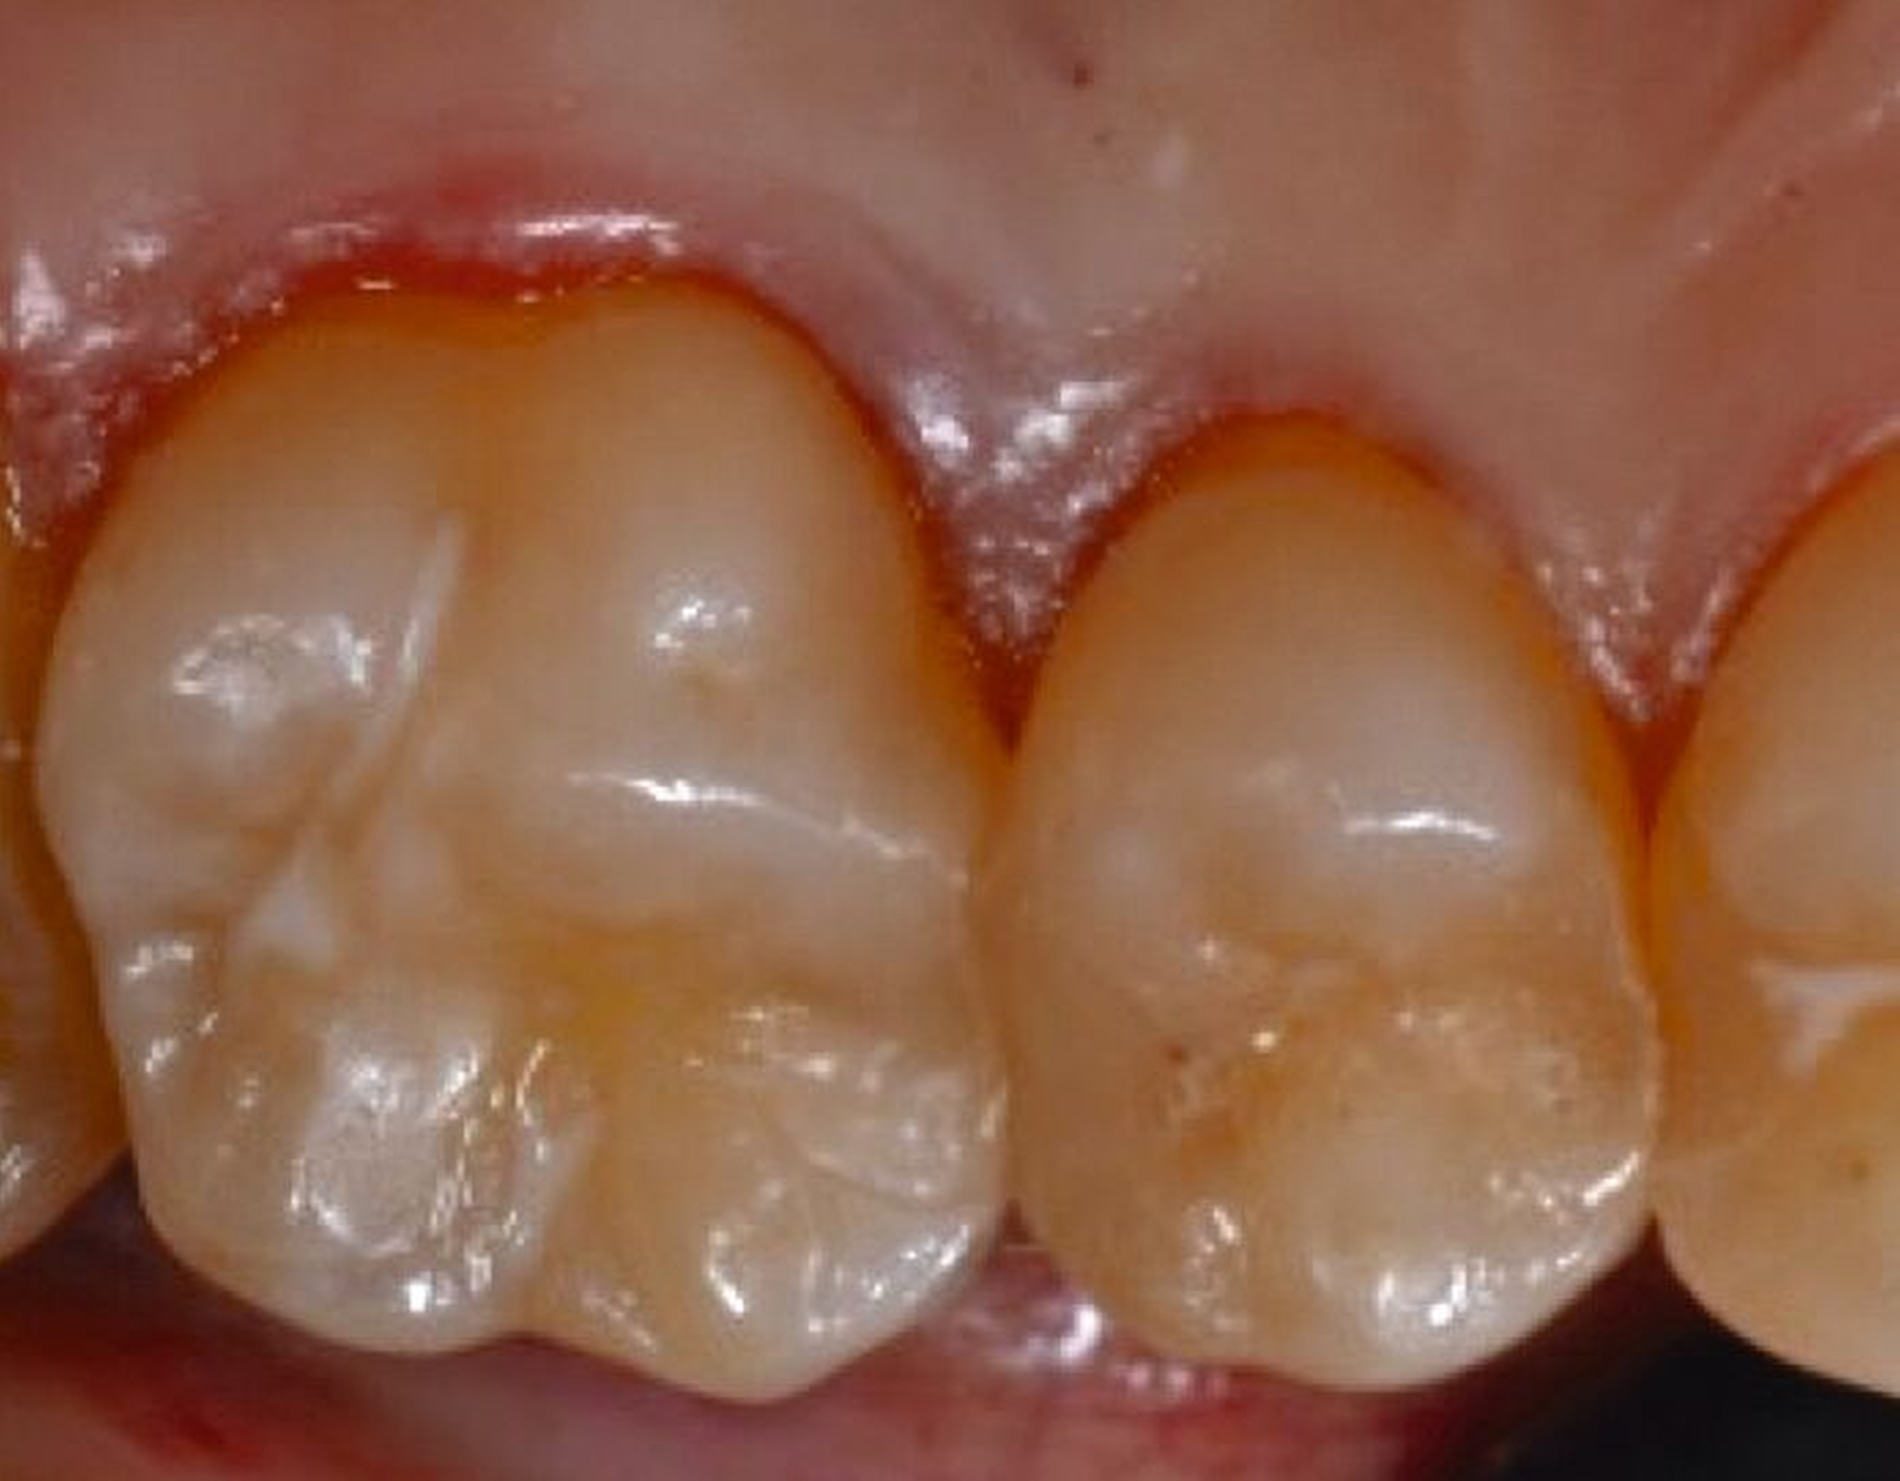

2. Auswahl des Zahnes

Ein adäquater Zugang zum Operationsbereich und auch für die zukünftigen Mundhygienemaßnahmen ist äußerst wichtig. Molaren mit Grad-II-Furkationsdefekten (mandibulär und bukkal maxillär) sind Kandidaten, die für ein regeneratives Verfahren infrage kommen. Basierend auf der verfügbaren Evidenz sind interdentale Grad-II-Furkationsdefekte an Oberkiefermolaren deutlich weniger geeignet, höchstwahrscheinlich aufgrund des eingeschränkten Zugangs. Weitere lokale Charakteristika können Auswirkungen auf die Ergebnisse der regenerativen Furkationschirurgie haben. Zum Beispiel können ein dickerer Phänotyp und das Fehlen einer Weichgeweberezession die Heilung nach GTR-Verfahren positiv beeinflussen. Günstigere Ergebnisse sind an Stellen zu erwarten, an denen das verbleibende approximale Knochenniveau koronal zum Eingang beziehungsweise zum Dach des Furkationsdefekts liegt, verglichen mit solchen, bei denen das approximale Knochenniveau auf der Höhe oder apikal des Furkationseingangs liegt. Ein enger interradikulärer Abstand kann eine gründliche Defektinstrumentierung beeinträchtigen. Das Vorhandensein einer Wurzelkanalfüllung ist nicht per se eine Kontraindikation für die Furkationsregeneration – vorausgesetzt, es gibt keine Anzeichen für apikale pathologische Veränderungen.

Fall 1 – einfach

Fall 2 – fortgeschritten

Fall 3 – komplex